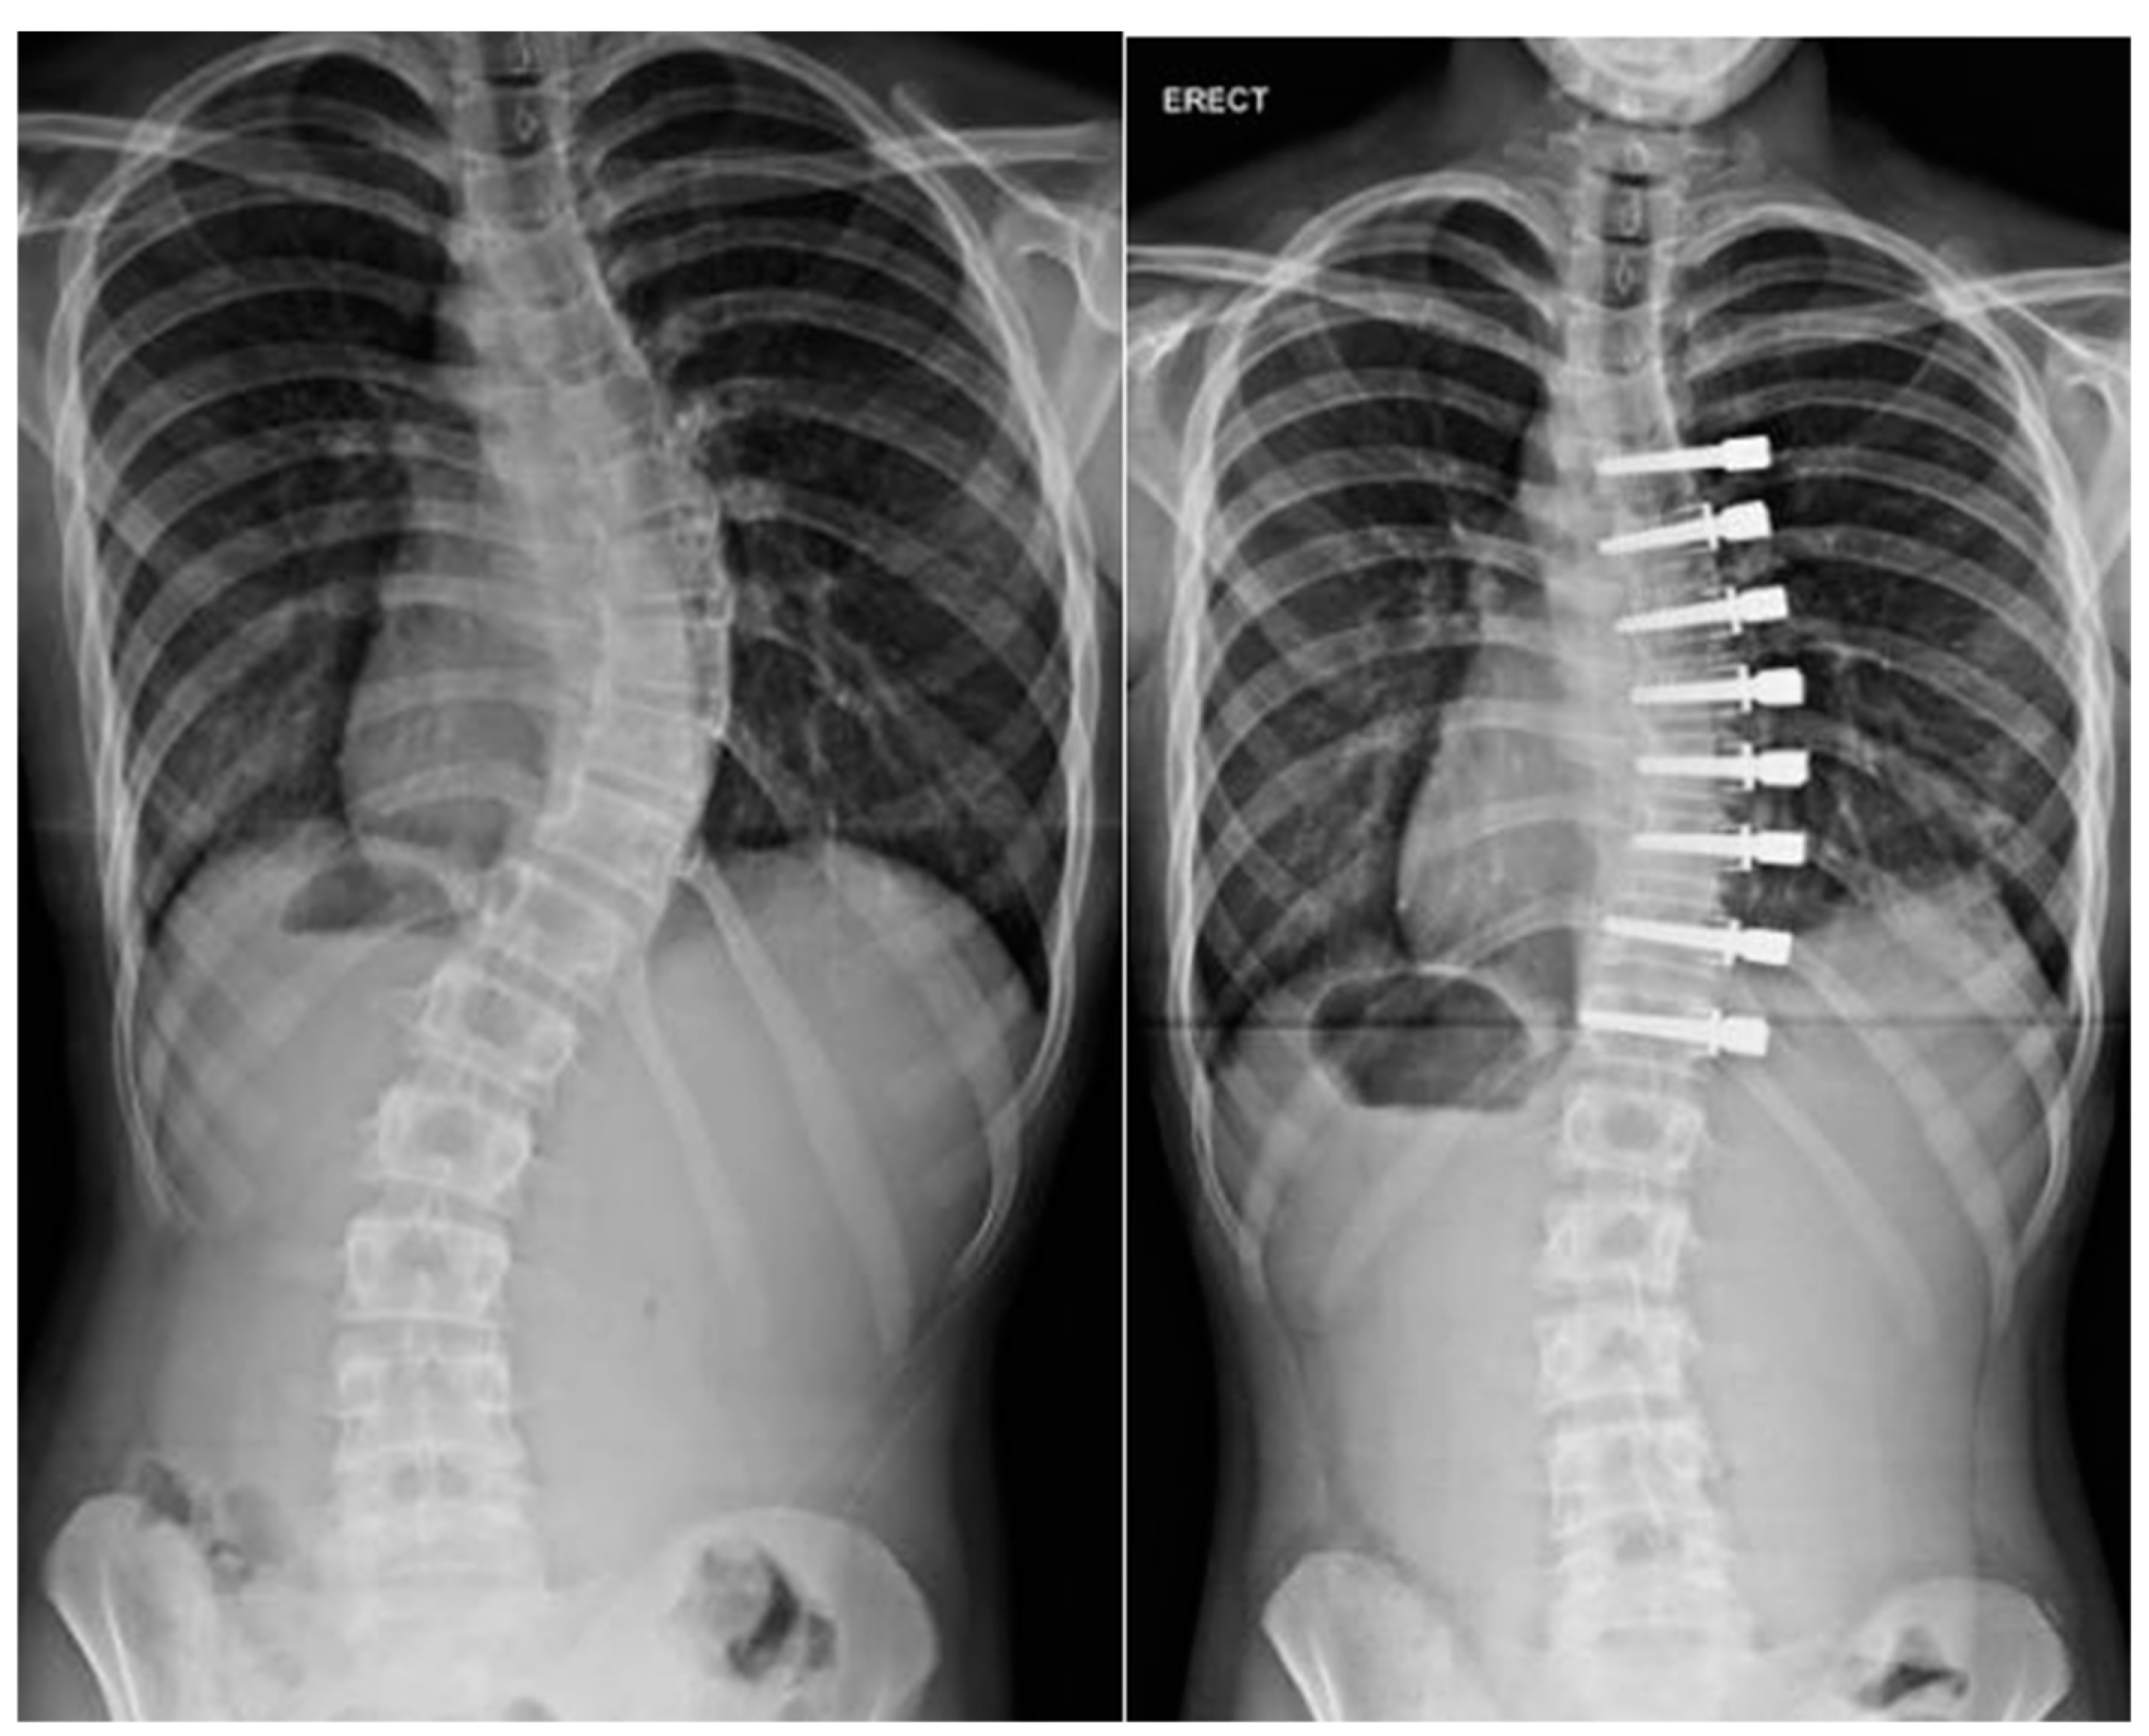

2. Non-Operative Treatment

Casting Technique

3. Bracing